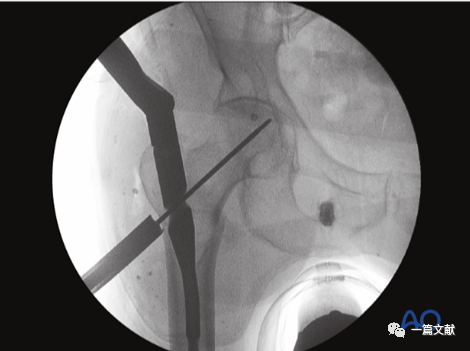

体位如下图,C臂机从水平位适度旋转,使透视射线与冠状面夹角约15°。

透视射线与患肢长轴夹角约30°-45°,如下图:

轴位片的作用:判断复位质量;观察头颈骨块与股骨干对线情况;确定导针准确的置入点。如下图:

从侧位片基础上抬C臂机约15°即轴位片,如下: